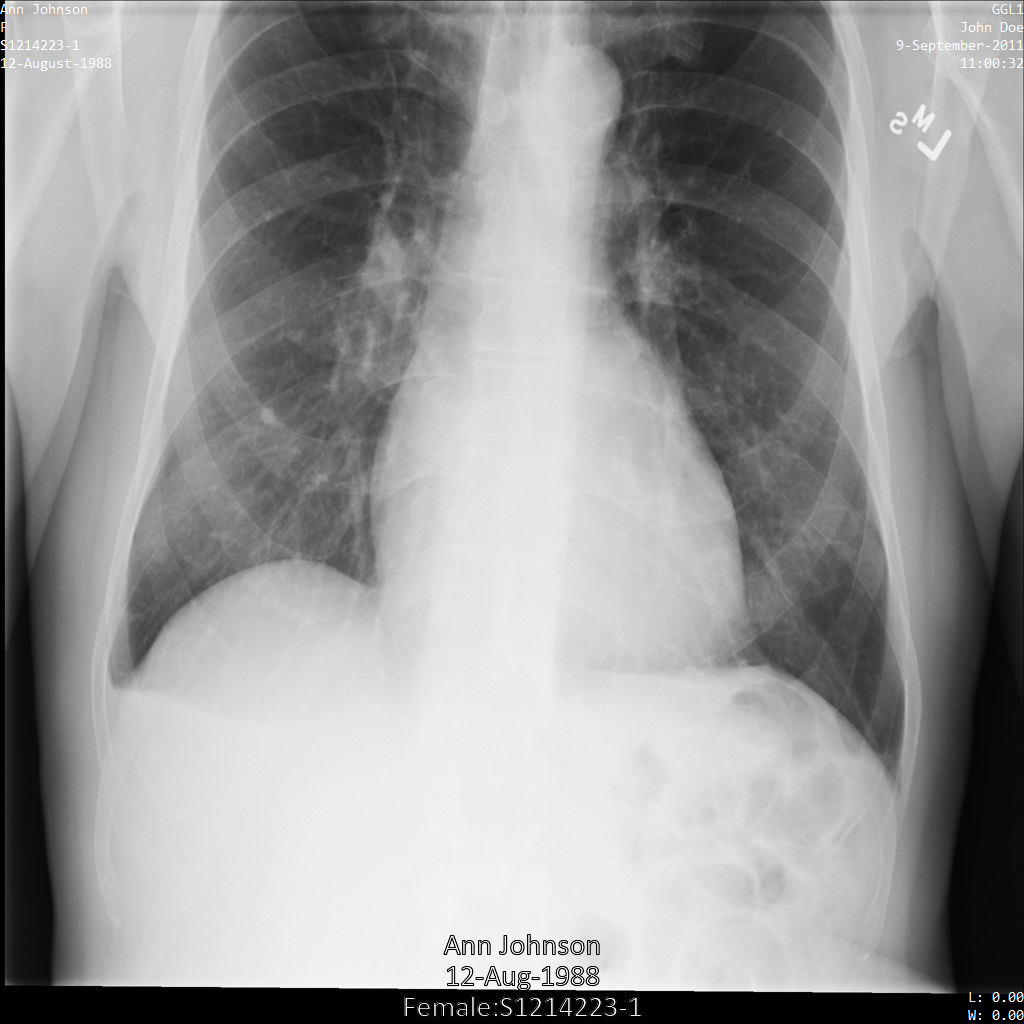

Vista geral dos samples

Os exemplos neste guia usam uma única instância DICOM, mas também pode remover a identificação de várias instâncias.

Cada uma das secções seguintes fornece exemplos de como remover a identificação dos dados DICOM usando vários métodos. É fornecida uma saída da imagem desidentificada com cada amostra. Cada exemplo usa a seguinte imagem original como entrada:

Pode comparar a imagem de saída de cada operação de desidentificação com esta imagem original para ver os efeitos da operação.